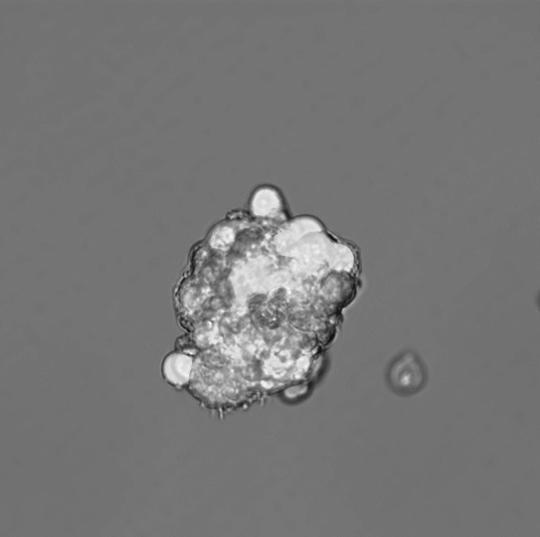

This image shows floating mammospheres containing breast cancer stem cells.

By observing cancer stem cells in a lab setting, they discovered that mitochondria are especially important for the proliferative expansion and survival of cancer stem cells, also known as 'tumour initiating cells', which would then promote treatment resistance.